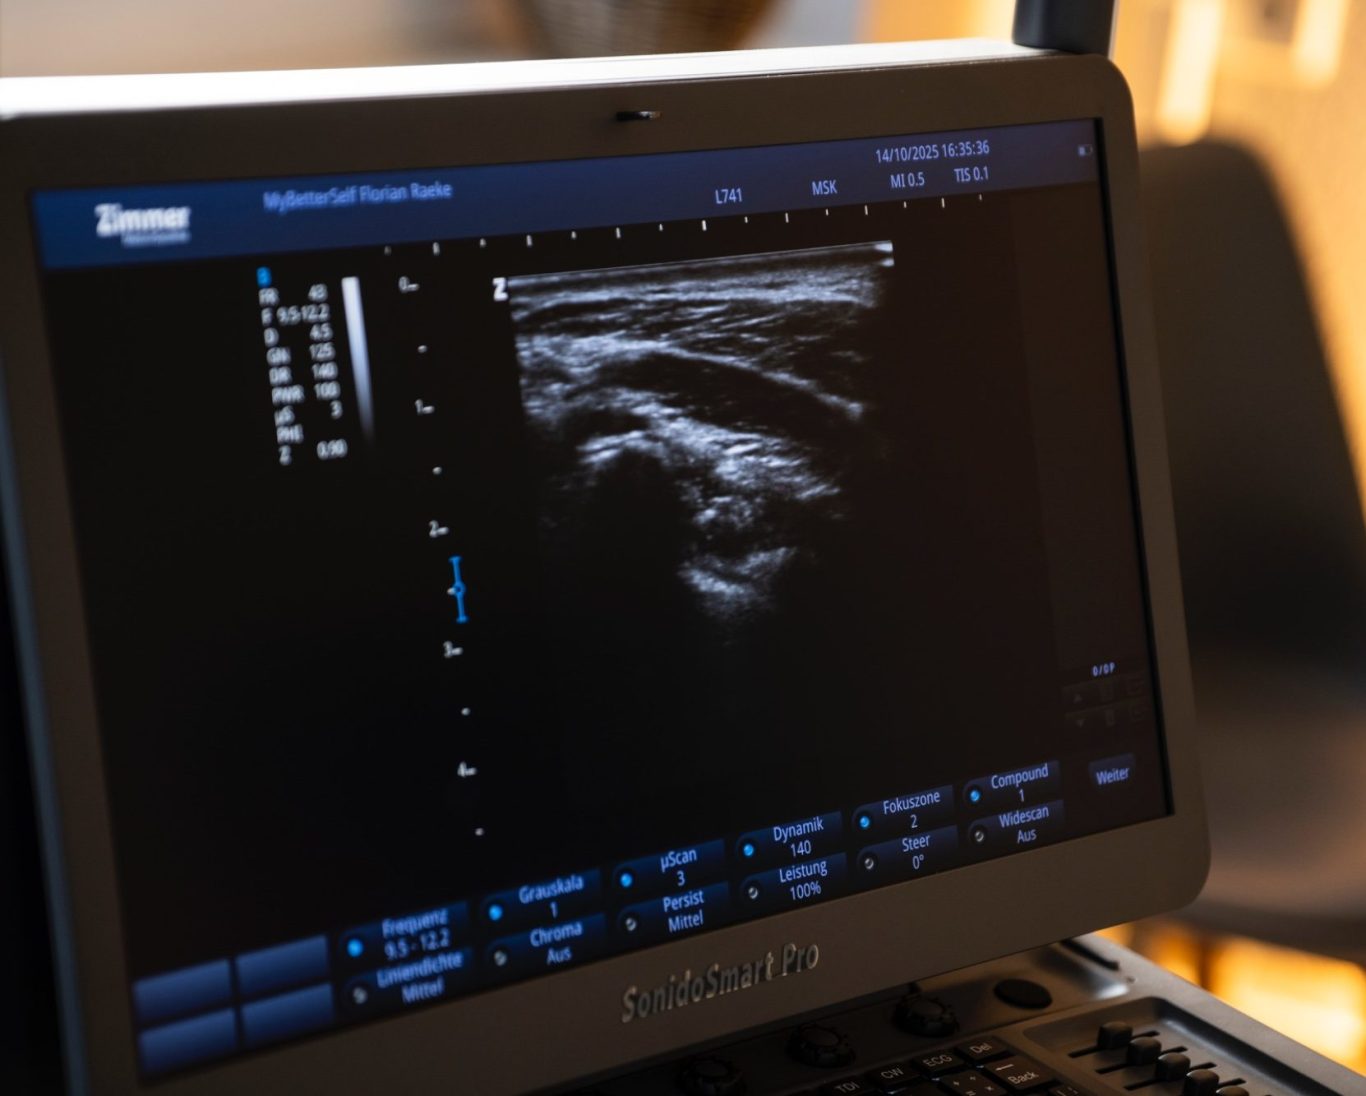

Beim Ultraschall werden hochfrequente Schallwellen ins Gewebe gesendet. Diese werden von den Strukturen unterschiedlich reflektiert und in echtzeitfähige Bilder umgewandelt.

So können wir direkt sehen, wie Muskeln arbeiten, ob Sehnen gereizt sind, ob Flüssigkeit oder Entzündungen vorhanden sind – ohne invasive Methoden.

Die Untersuchung dauert nur wenige Minuten und findet direkt in der Praxis statt. Ein kleiner Schallkopf wird über die betroffene Region geführt, teilweise auch während bestimmter Bewegungen, um funktionelle Zusammenhänge sichtbarzu machen.

Diagnostischer Ultraschall ist in klassischen Physiotherapiepraxen eher unüblich. Bei MyBetterSelf setzen wir ihn gezielt ein, um präzise Diagnosen, individuelle Therapien und nachhaltige Verbesserungen zu ermöglichen.